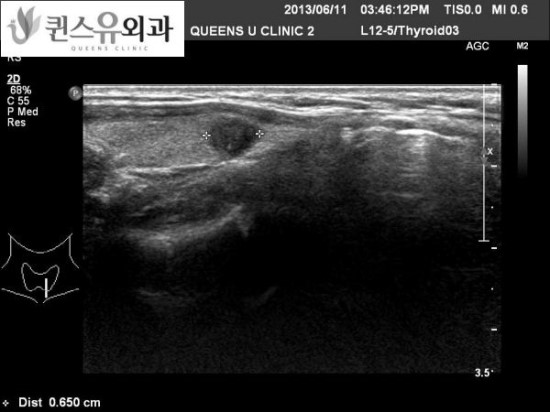

내원하신 환자의 초음파 사진 1

그 증상은 암으로 의심되어 갑상선을 조사했더니 아니나 다를까 좌갑상선 전체가 암처럼 보였습니다.

갑상선 세침 흡인 세포 검사를 실시하고 경부 림프선에 대해서도 세포 검사를 실시했습니다.